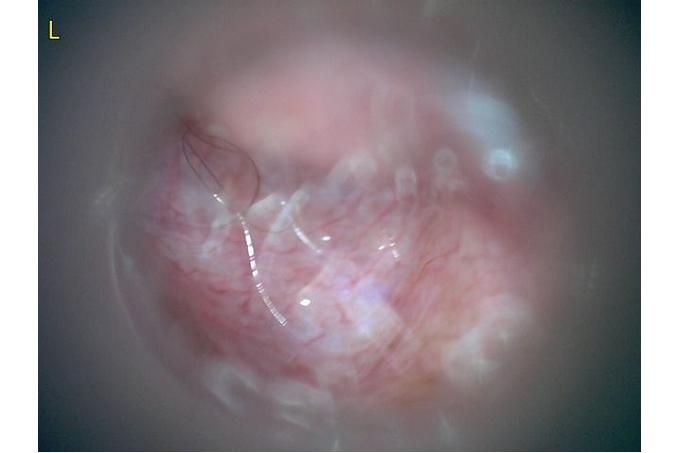

오늘 낮과 방금 5분전에 일어난 일인데요.. 강아지 귀질환 중에.. 옷입히고나서 귀를 바닥에 대고 비비거나, 귀에 통증을 호소하면서 잠깐 비틀비틀 걷는 경우 이런 경우 대체 뭘까요? 외이염일때도 이럴수도 있을까요? 아니면 중이염 내이염일지.. 한 2~3분정도 통증을 호소하다 지금은 또 정상이 됬는데 옷입을때만 옷의 목카라 부분이 귀에 닿을때 문제가 되는 느낌입니다. 평상시엔 가끔 양쪽 귀를 긁거나 귀를 자주 터는 정도입니다. 특이사항은 오른쪽귀 솜 돌돌 말아 귀안에 넣어줘도 비명을 지르며 엄청 아파하는데(작년11월경) 왼쪽은 안아파합니다)

그리고 용종이라고 코멘트 달아주셔서 저 검이경 사진 찍은곳에 물어보니 용종은 아니라고합니다.

저 부분 용종 아니라합니다

제가 가장 알고싶은점은. 저렇게 옷깃에 귀가 시쳐도 아파할정도면 이게 외이염일까요 중이염일까요 내이염일까요? 얼마나 아픈지 옷한번 얇은 내복 평상시 입던거 입히면 입히고 나서 바로 온집을 돌아다니면서 바닥에 귀를 대고 정신나간애처럼 비비고 비틀비틀 걷습니다 그러다가 2~3분후 다시 정상으로 돌아옵니다

(근데 또 귀를 조물락 조물락 만져도 안아파합니다, 다만 솜을 길게 해서 넣으면 솜만 넣어도 아파합니다 특히 오른쪽요 왼쪽은 안아파합니다)